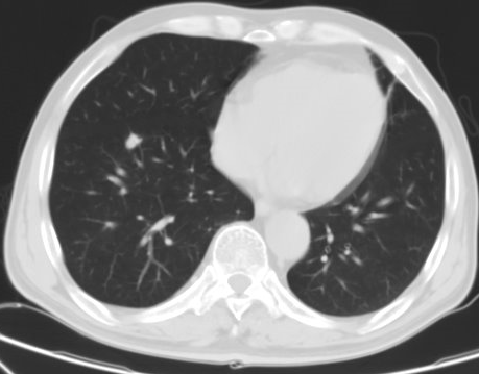

2018.07.20:

疗效评价:

影像学评价:PD